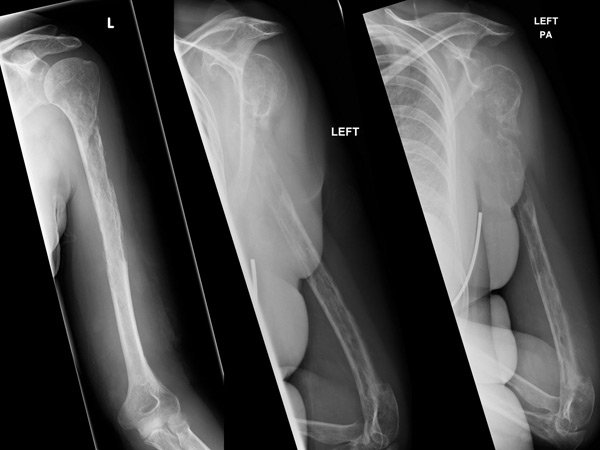

ఎన్నడూ కానీ వినీ ఎరుగని రీతిలో, ఎక్స్- రే నివేదిక ద్వారా నెమ్మదిగా సమయానుసారం ఎముకలు అదృశ్యమవడం కనపడడంతో వైద్యులలో కలవరం మొదలైంది. దీనిని గుర్తించడానికే నెలల సమయం పట్టింది అంటే వైద్యుల కే అంతుచిక్కని సమస్య అని చెప్పకనే చెప్తుంది.

44 సంవత్సరాల వరకు ఎటువంటి సమస్యలు లేకుండా ఎంతో ఆరోగ్యంగా ఉన్న మహిళ, ఒక్కసారిగా ఎడమ భుజం లో నొప్పి అంటూ వైద్యుని సందర్శించింది. ఎక్స్- రే పరీక్షా సమయంలో వైద్య సిబ్బంది, చేతి పై భాగాన అసాధారణంగా పెరిగిన ఎముకల కారణంగా కణితి గా భావించి, దీనిని కాన్సర్ గా అపోహ పడ్డారు. కానీ బయాప్సీ నివేదికలో అది కాన్సర్ కాదని తేలింది. కొన్ని నెలల తర్వాత చేసిన మరో బయాప్సీలో నిరపాయమైన రక్త నాళపు కణితి ఉన్నట్లు అర్ధమైంది. ఆ కణితి ఎలాంటిదో కూడా అనేక పరీక్షలు చేశాక కానీ అర్ధం కాలేదు. కానీ, రక్త నాళాలు పెరగడం కాదు కానీ, ఎముకలు కనపడకుండా పోవడం వైద్యులను కూడా ఆశ్చర్యానికి గురిచేసింది.

ఆ మహిళ శరీరం లోని అనూహ్య మార్పుల కారణంగా, వాపు, నొప్పి నెలల వ్యవధిలో పెరుగుతూ వచ్చింది. క్రమంగా చిన్ని చిన్ని సమస్యలకే ఎముకలు విరగడం ప్రారంభమైంది. 18 నెలల వైద్యుల పర్యవేక్షణలో, ఎముకలు నెమ్మదిగా సమయానుసారం అదృశ్యమవుతున్నాయని తేల్చారు. తద్వారా అస్థి , మృదులాస్థి ఎముకలు రెండూ నెమ్మదిగా తగ్గుతూ రావడం గమనించారు . మరియు ఎముకలు పెరగాల్సిన ప్రదేశాలలో రక్తనాళాలు పెరగడం కనిపించింది.